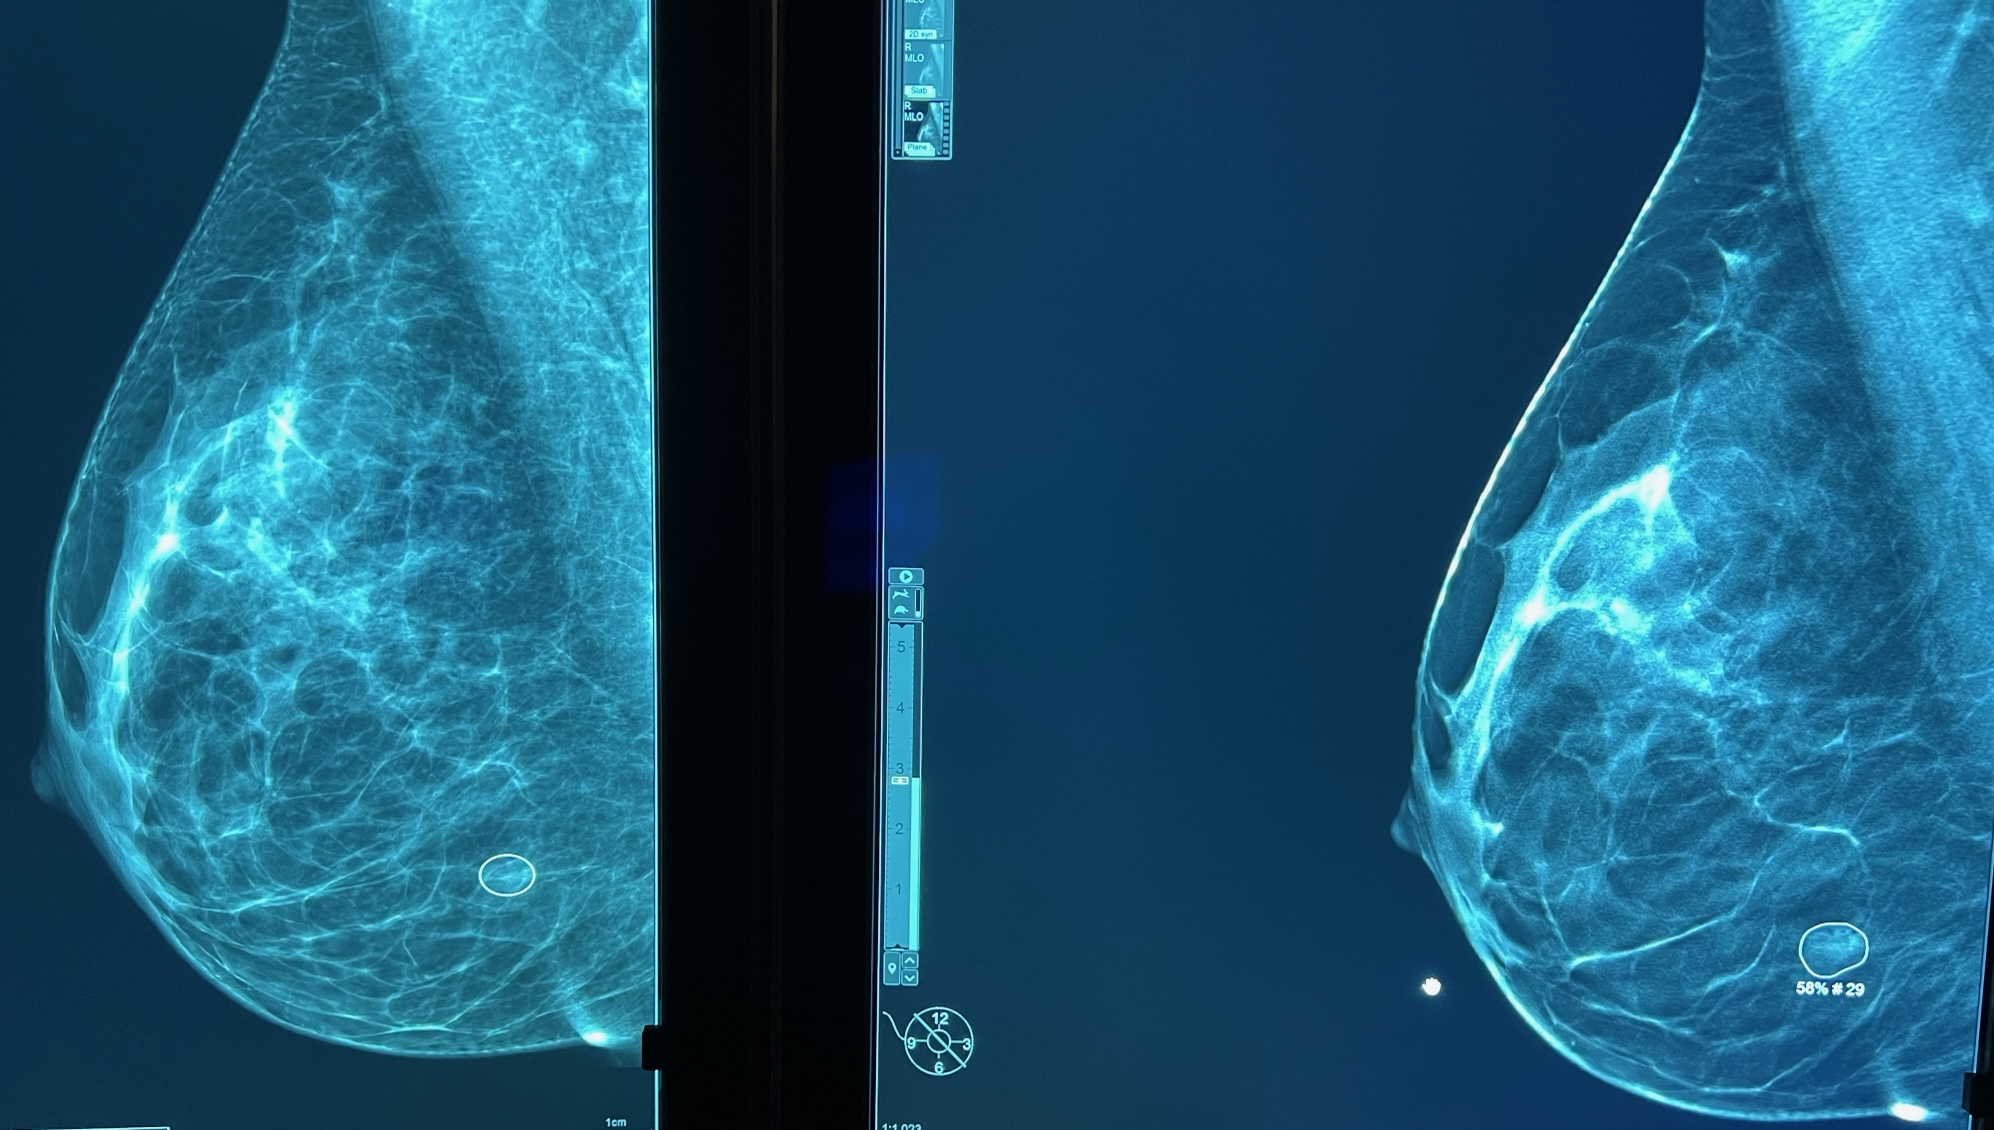

Le radiologue lit votre mammographie et dans un second temps utilise sur le mammographie numérique un CAD (computed aided detection), de dernière génération (ICAD pour imagerie 2D et tomosynthèse 3D) qui va marquer les micro-calcifications (marquées par un carré) et les masses (marquées par un rond) avec la valeur prédictive positve en faveur d'une lésion maligne.

Micro-calcifications (carré) Petite masse, distorsion architecturale (rond)

Valeur prédictive de lésion maligne 58%